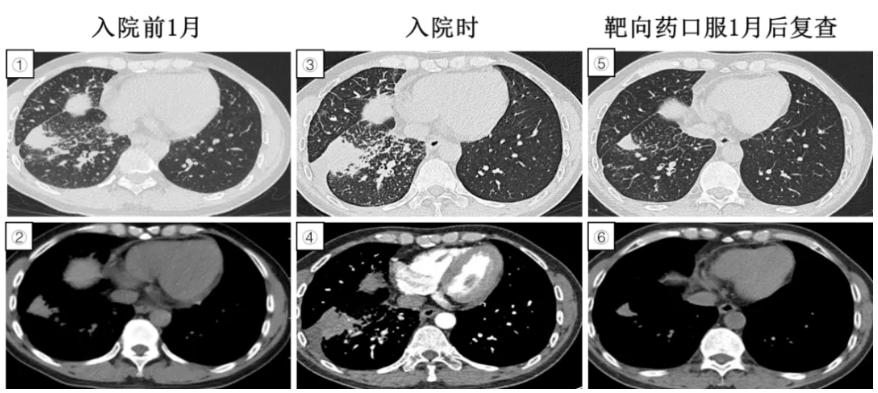

图1:①-②入院前胸部CT无特殊异常。③-④入院后3天突发严重低氧血症,CT肺动脉造影提示双肺磨玻璃样渗出影,呈现“暴风雪样”特征,双下肺后背部坠积性肺炎改变,肺动脉未见充盈缺损。⑤-⑥脂肪栓塞治疗6天复查胸部CT提示渗出影较前明显消散,可见散在“铺路石样”改变。

入院3天后,突发氧饱和度下降至78%,储氧面罩10L/分吸氧下SpO2 97%,急诊CT肺动脉造影未见肺动脉栓塞,双肺弥漫性磨玻璃渗出影,“暴风雪样”改变。

治疗经过:予以高流量吸氧、甲强龙40mg静滴BID、低分子肝素抗凝等治疗2天后氧合明显改善,气急缓解,6天后复查CT肺动脉结果提示磨玻璃影较前部分消散,可见散在“铺路石样”改变。

疾病要点:脂肪栓塞综合征是脂肪或骨髓颗粒释放入血液循环后出现的临床综合征,与急性呼吸窘迫综合征相似,为快速发生的严重低氧血症,常伴有神经系统异常和皮肤瘀斑,最常见于骨科创伤长骨和骨盆骨折引起。胸部影像改变的病理基础是循环中的脂肪滴栓塞肺小血管,引发炎症性肺损伤,导致毛细血管通透性增加、肺泡水肿、出血和肺不张,其本质是一种急性肺损伤,典型改变为两肺弥漫性斑片状阴影,称之为“暴风雪样”改变,也可表现为间质性水肿和肺泡性病变”混合存在的“铺路石样”改变。治疗上目前尚无有效药物可直接溶解脂肪,消除脂栓,所以均以对症治疗为主,强调早预防。糖皮质激素和白蛋白可能有一定改善使用,激素能减轻游离脂肪酸对呼吸膜的毒性作用,减少肺间质水肿和脑水肿,白蛋白能与游离脂肪酸结合,降低其毒性作用。